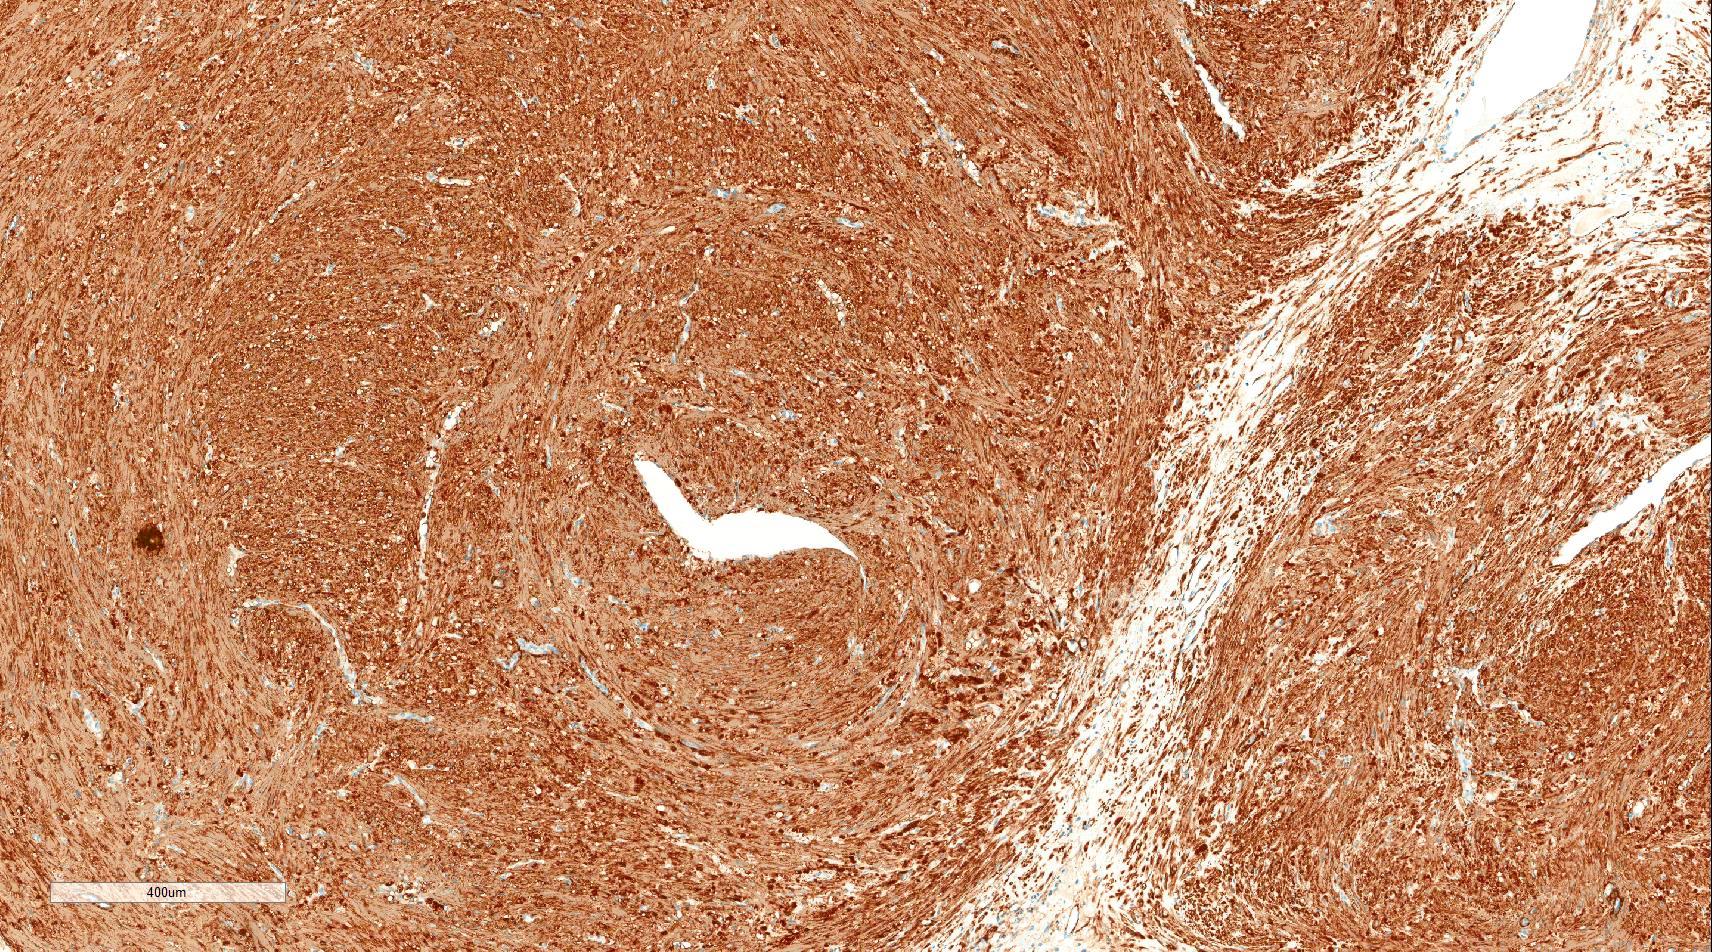

- Encapsulated proliferation of eosinophilic smooth muscle cells with minimal nuclear pleomorphism

- Rounded or slit-like veins with muscular walls present within the tumor (J Cutan Pathol 2017;44:342)

- Venous type: thick walled vessels that are easily distinguished from the intervascular smooth muscle

Microscopic (histologic) images

Contributed by Ohoud Aljarbou, M.D., Jijgee Munkhdelger, M.D., Ph.D. and Andrey Bychkov, M.D., Ph.D.

Positive stains

- Actins (alpha smooth muscle actin and HHF35) and calponin (diffuse positivity) and diffusely or focally positive for h-caldesmon